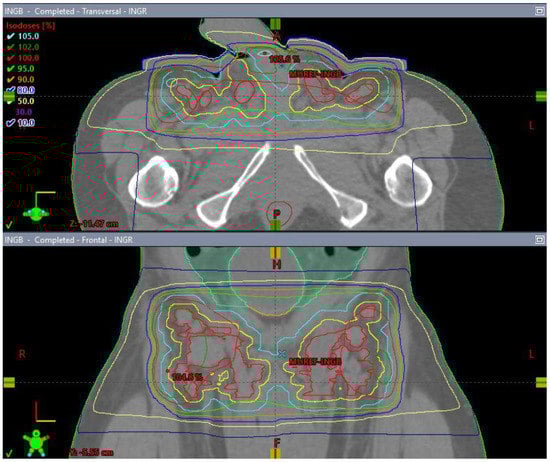

Figure 10.

3 Field (2 laterals (A,B) and 1 posterior (C) field) palliative radiation plan with 20 Gy/5 fractions to the inguinal nodes with a 1 cm bolus (D).